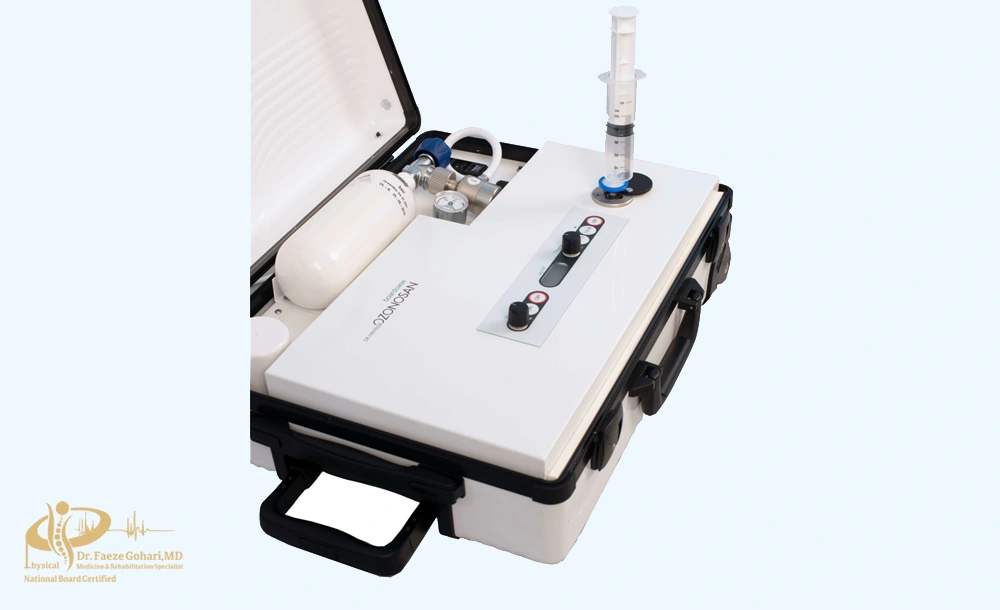

آمادهسازی گاز اوزون

برای اوزون تراپی مفصل زانو، از گاز اوزون پزشکی استفاده میشود که باید در لحظه تزریق و بهصورت تازه تولید شود. این گاز از ترکیب اکسیژن پزشکی (O₂) با استفاده از دستگاههای مخصوص اوزونساز تولید میشود. دستگاه، اکسیژن را به گاز اوزون (O₃) تبدیل میکند و به پزشک امکان میدهد تا غلظت موردنظر را تنظیم کند.

غالباً غلظت اوزون برای تزریق مفصلی بین ۱۰ تا ۳۰ میکروگرم بر میلیلیتر در نظر گرفته میشود. انتخاب این مقدار به عوامل مختلفی مثل شدت التهاب، مرحله آرتروز و وضعیت عمومی بیمار بستگی دارد.

پس از تولید، گاز اوزون به سرعت داخل سرنگ استریل کشیده میشود، چون نیمهعمر کوتاهی دارد و در مدتزمان کوتاهی ناپایدار میشود. به همین دلیل، تمام این فرآیند باید با دقت بالا، در محیطی کاملاً استریل و تحت نظارت پزشک یا تکنسین آموزشدیده انجام شود. این آمادهسازی معمولاً در اتاق تزریق و همزمان با حضور بیمار انجام میگیرد تا از تازگی و دقت غلظت گاز اطمینان حاصل شود.